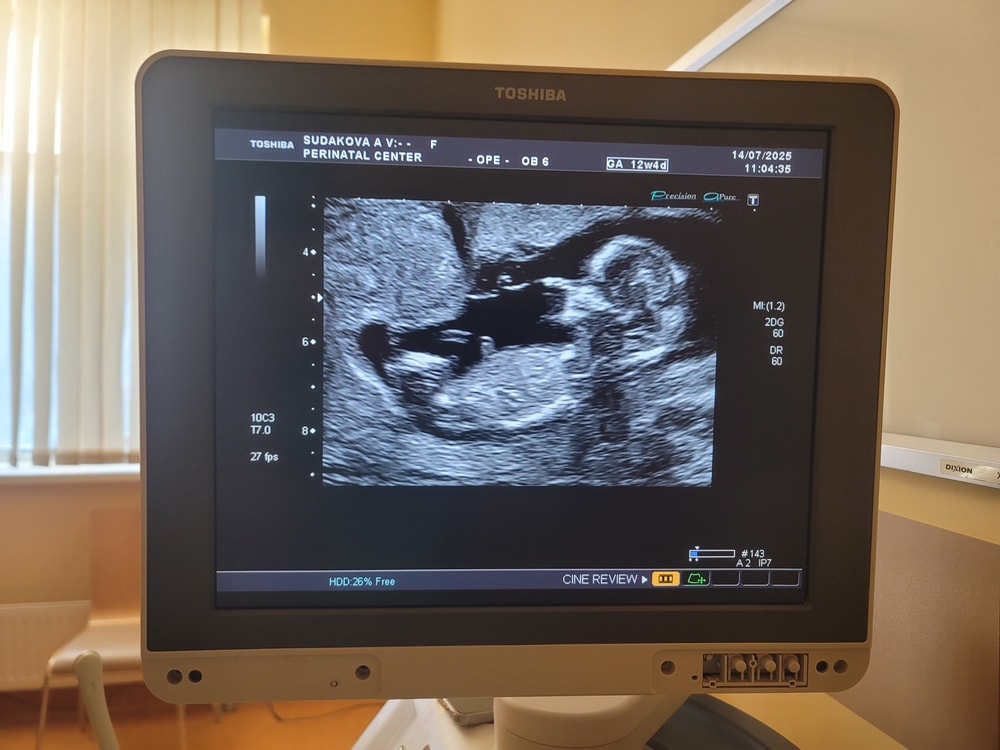

Первый скрининг

Анализы, скринингиГлавное - по узи всё хорошо!)

Сегодня 12,4, а по ктр 13,1 недель, что необычно для меня. Старшие были точно по размеру, или отставали. А этот малыш опережает. Крупный будет?

Разрешили сделать фото, что уже хорошо. Пол не предполагали, мне кажется мальчик)